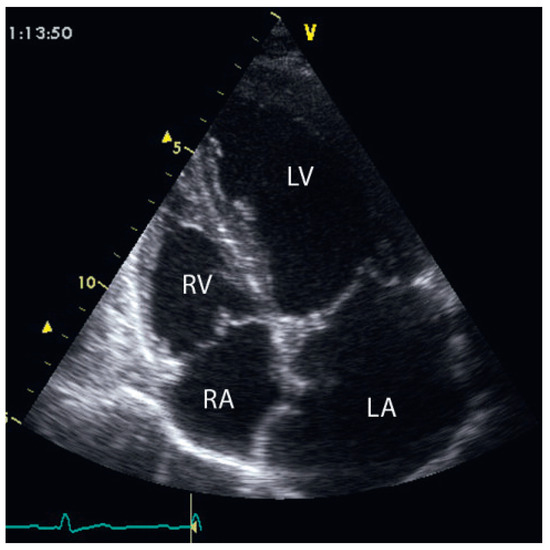

Fallbericht